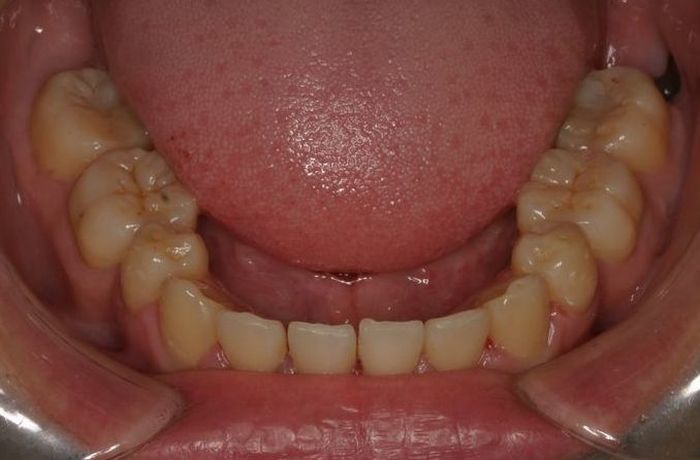

Case 3

主訴:  八重歯が気になる。

診断:  アングルⅠ級 叢生

治療方針:

患者さんは19歳の男性であった。上下顎左右側犬歯の低位による審美障害を訴えた。第一大臼歯はⅠ級の咬合様式であったことから上下顎左右側第一小臼歯の抜歯とホールディングアーチによる加強固定を行い、セクショナルアーチを用いて上下顎左右側犬歯を歯列内に誘導し、咬合関係の改善を図ることとした。

治療期間: 1年3カ月

費用:

診断費30000円、装置費用600000円、保定装置費用50000円、月1回の調整費4000円  (全て税別)

【 治療前 】

【 治療後 】